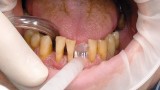

Jedną z popularniejszych metod stabilizacji zębów rozchwianych jest ich szynowanie. Metoda ta, wspierająca inne metody leczenia, jest powszechnie stosowana. Jednym z najnowocześniejszych materiałów wykorzystywanych w stomatologii do szynowania zębów jest taśma poliaramidowa. W opisanym przypadku autorzy pracy przedstawiają sposób uproszczenia całej procedury i ograniczenia ryzyka popełnienia błędu, szczególnie w sytuacji całkowitej utraty zęba. Uzyskano to dzięki zastosowaniu indeksu wykonanego z przezroczystego silikonu.

One of the more popular methods of stabilising loose teeth is to splint them. This method, aiding other methods of treatment, is generally used. One of the most modern materials used in dentistry for splinting teeth, is polyamide tape. In the case described the authors show how to simplify the whole procedure and limit the risk of making a mistake, particularly in the situation of total loss of one tooth. This was achieved thanks to the use of an index made out of transparent silicone.